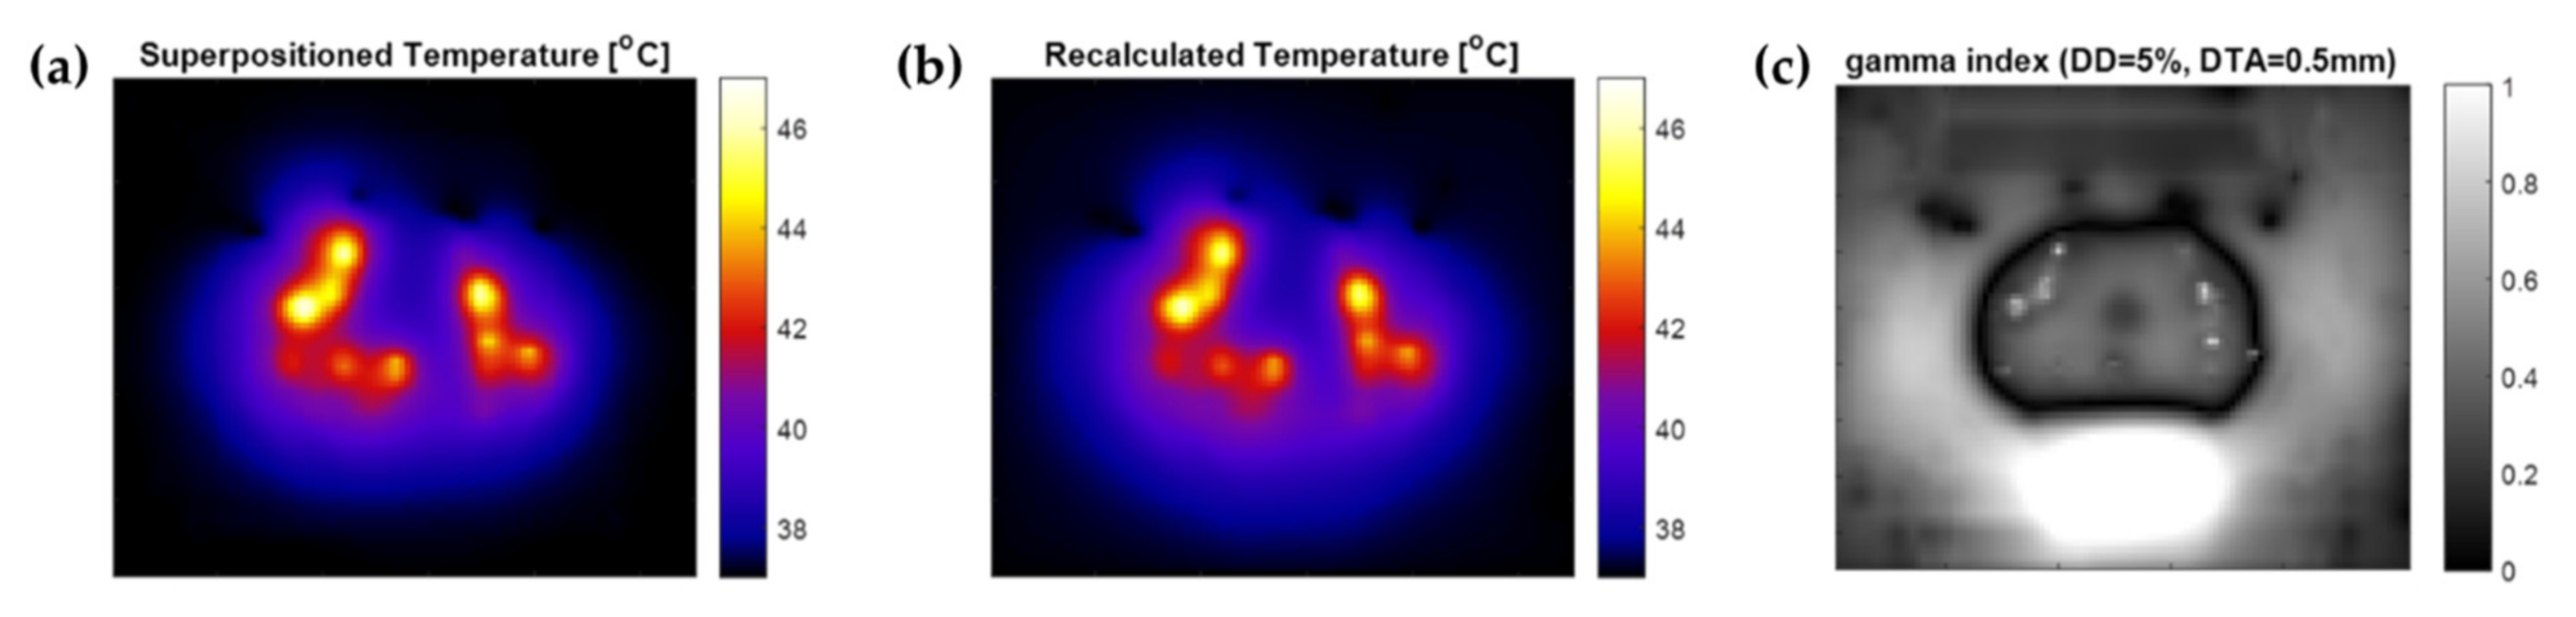

2.8. Temperature Superpositioning Validation

3.1. Temperature Superpositioning Validation